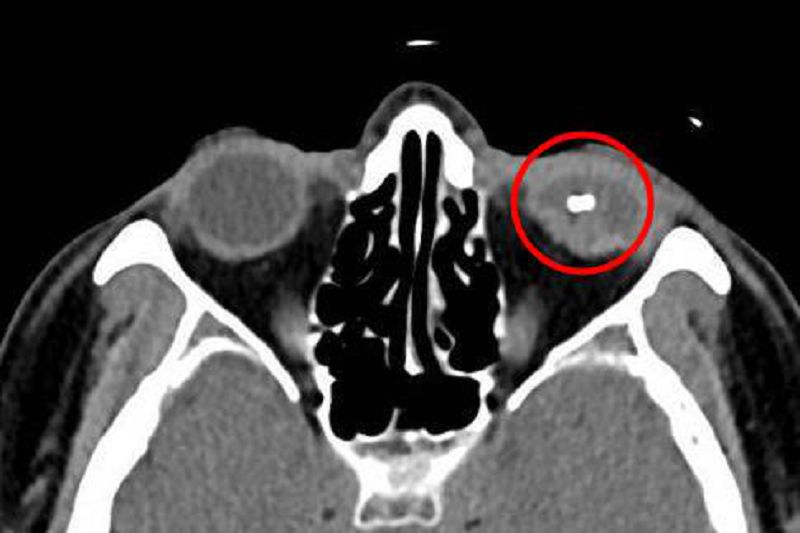

大部分割草機意外的患者因眼睛內部出血,醫師進行手術時可能較難辨認硬物的位置,導致夾取困難;若經電腦斷層(CT)檢查後確認為金屬物質,則可使用「電磁鐵」吸出,再清理傷口。何明山指出,甚至有少部分未出血的患者不知道眼睛內已存在異物,僅以為碰撞疼痛後休息一下就會慢慢恢復,並未立即就醫,不僅滯留在眼睛內的東西可能造成感染,若異物是鐵片,還會因氧化釋出對視神經和視網膜具有毒性的鐵離子,使視力受損。